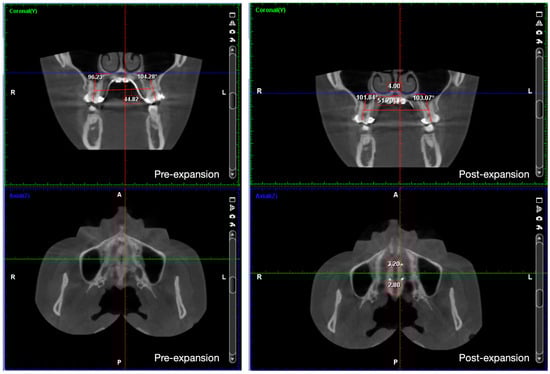

- Liao, Y.C.; Ho, K.H.; Wang, C.W.; Wang, K.L.; Hsieh, S.C.; Chang, H.M. Skeletal and dental changes after microimplant-assisted rapid palatal expansion (MARPE)—A Cephalometric and Cone-Beam Computed Tomography (CBCT) study. Clin. Investig. Orthod. 2022, 81, 84–92. [Google Scholar] [CrossRef]